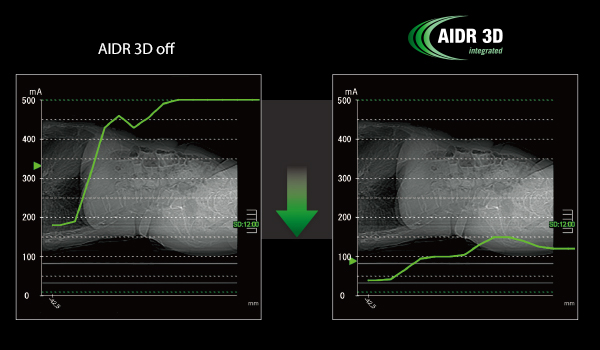

Комплексное снижение дозы облучения — это работает

Итеративная реконструкция

текущей программы модуляции SUREExposure 3D, исключая догадки об оптимальной дозы облучения для пациента. Доза облучения автоматически уменьшается до 75%.

- AIDR 3D Расширенная реконструкция